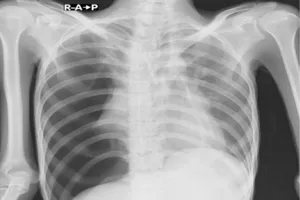

10. 기흉

가슴 통증이 갑자기 발생하고 호흡이 가빠진다면, 기흉을 의심해 볼 수 있습니다. 기흉은 폐에서 공기가 새어 나와 흉강에 차면서 폐가 쪼그라드는 질환으로, 마치 풍선에 구멍이 난 것처럼 폐에 공간이 생기는 현상입니다. 특별한 원인 없이 발생하는 경우가 많으며, 마르고 키가 큰 남성에게서 자주 나타납니다. 기흉의 치료는 질병의 정도에 따라 다르지만, 조기에 발견하고 적절한 치료를 받으면 대부분 완치될 수 있습니다. 따라서 가슴 통증이 지속되거나 호흡이 불편하다면 즉시 병원을 방문하여 정확한 진단을 받고, 필요한 치료를 받는 것이 중요합니다.